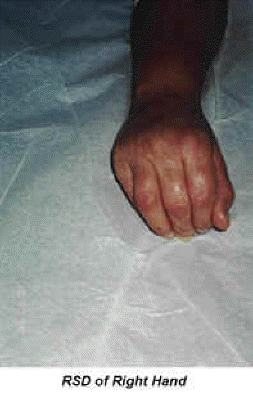

Hand Deformity Picture #1 RSD of the right hand with deformity.

Hand Deformity Picture #2 The wrist and digits became fused. The patient was not able to move the wrist or digits.